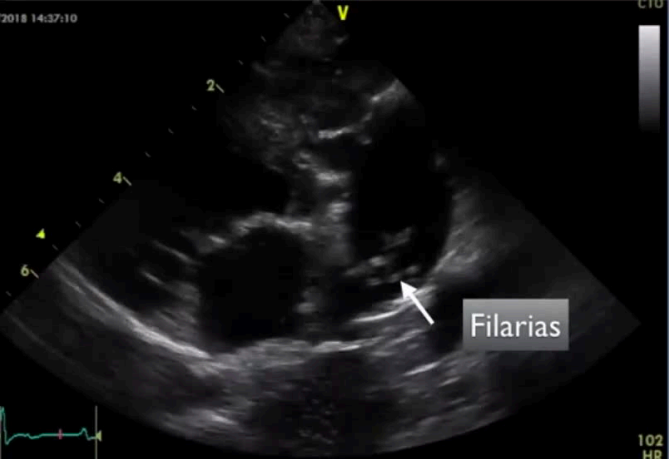

Patologías más frecuentes

Enfermedad valvular mixomatosa mitral

- Degenerativa y progresiva.

- Afecta la válvula mitral, que se engrosa y deforma por acumulación de material mixomatoso.

- Provoca regurgitación mitral, con flujo retrógrado hacia la aurícula izquierda durante la sístole.

- Conduce a sobrecarga cardíaca e insuficiencia cardíaca.